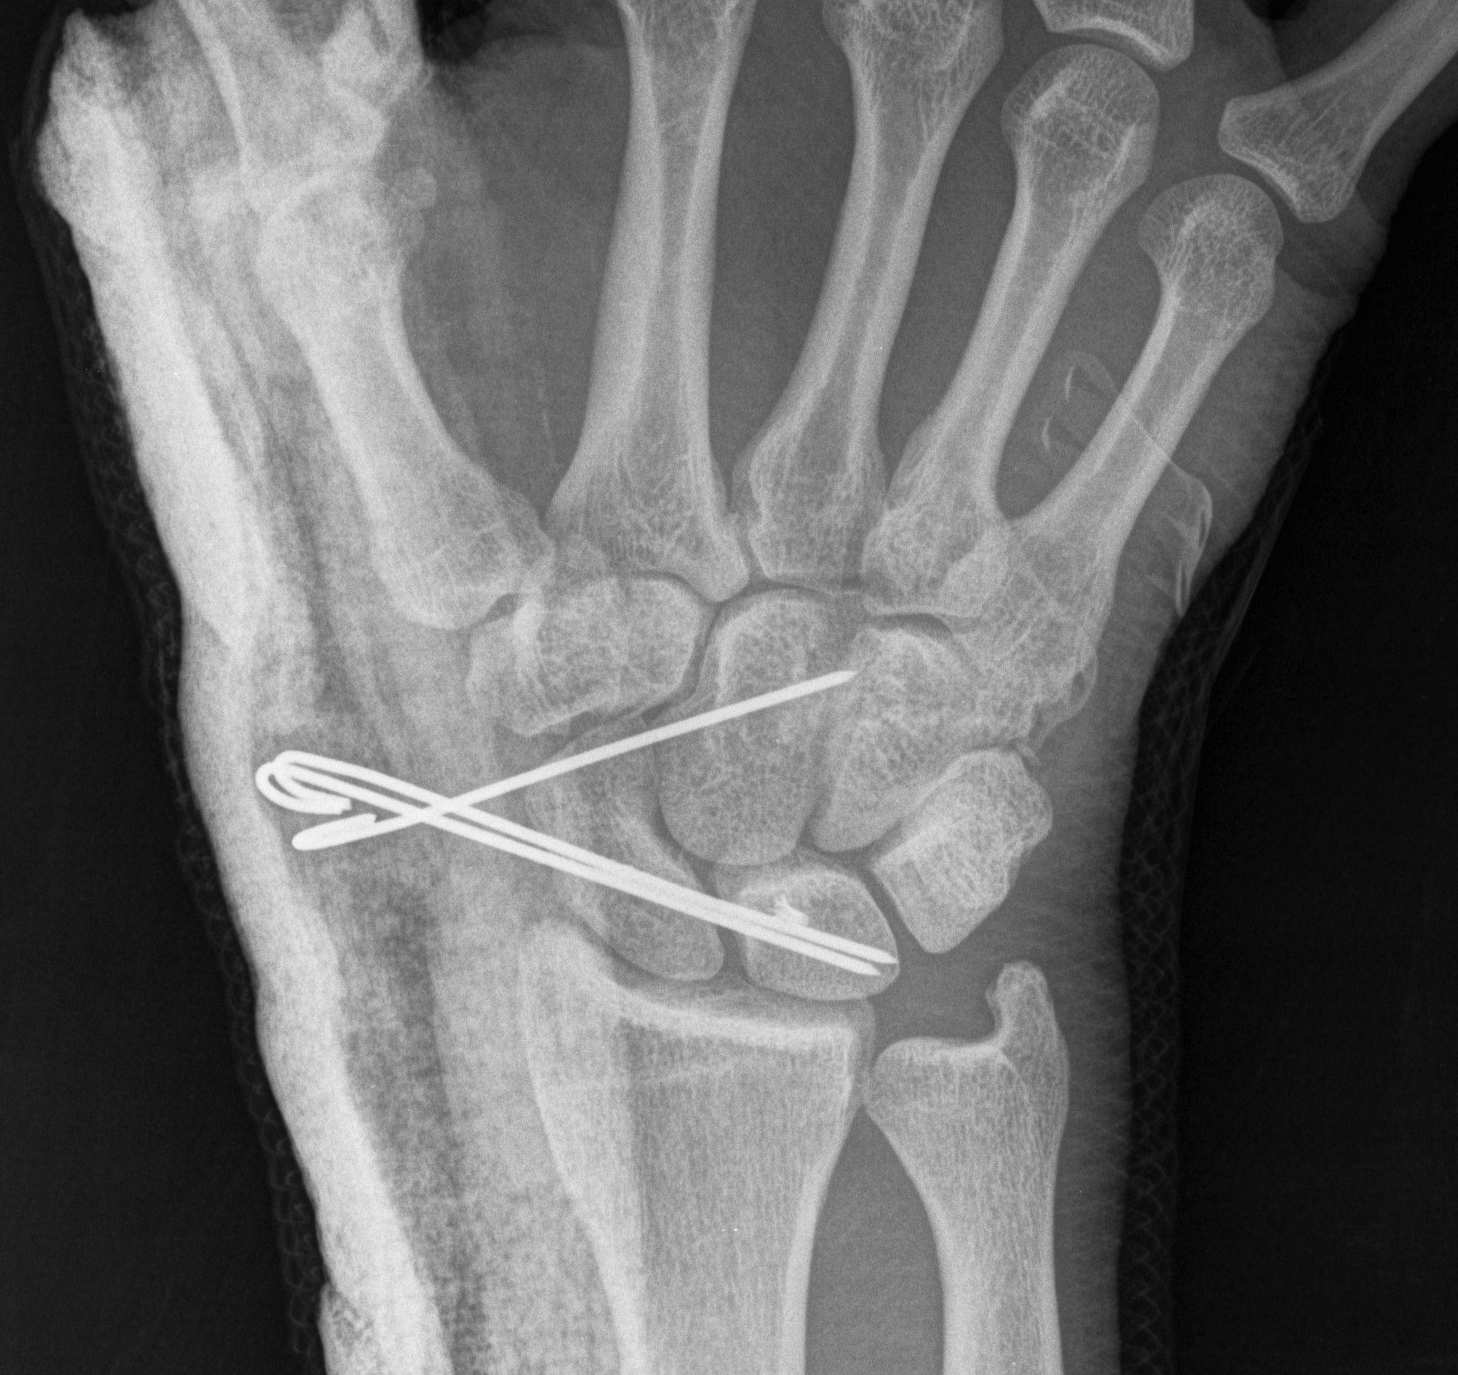

X-ray

Disruption of Gilula's 3 smooth carpal arcs

- K wires SC / SL / LT (areas of ligament rupture)

- K wires LT and TC (SL ligament is intact)